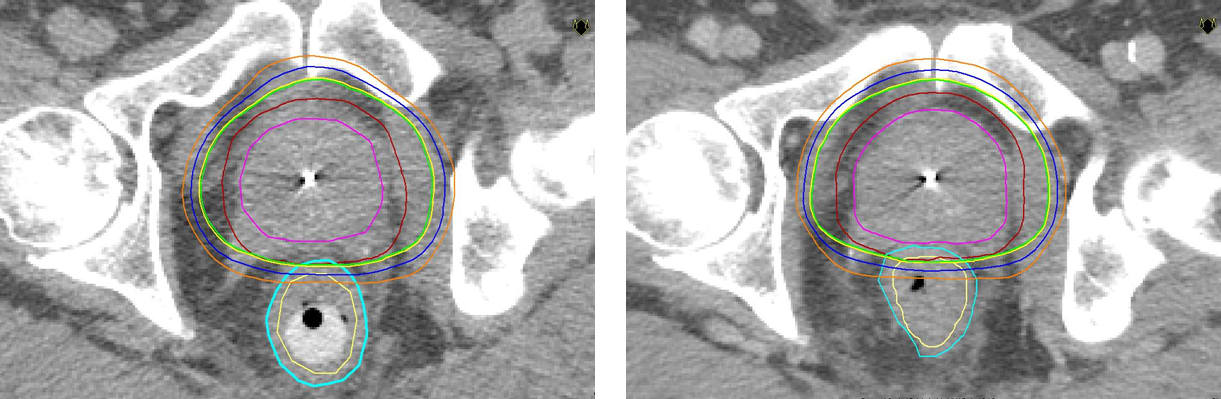

– Precis som vid annan strålterapi är målet med stavbehandling att döda cancercellerna. Vi behandlar 25-30 patienter per år med denna metod. Fördelen är att man kan öka avståndet mellan prostata och ändtarmen och därigenom ge högre stråldos i prostata och lägre i ändtarmen så att frisk vävnad skonas. Jämfört med konventionell strålbehandling utan rektalstav, som är vanligast idag, kan man ge lite högre stråldos utan fler biverkningar, säger Kristina Nilsson, överläkare i onkologi vid Akademiska sjukhuset.

Strålning är ett vanligt sätt att behandla prostatacancer, både när cancern är kvar i prostatan och när den spridit sig till andra delar av kroppen. Vid tidig sjukdom, när tumören inte spridit sig utanför prostatakörteln, är strålning ett likvärdigt alternativ till kirurgi som botande behandling. Forskning har visat att ju högre stråldoser man kan ge tumören, desto större är chansen till bot. De doser som fortfarande användes för något decennium sedan var ofta inte tillräckligt höga för att bota patienten. Det finns nu en stark strävan att utveckla metoder som gör att man kan öka stråldosen utan att förvärra biverkningarna.

* Rektalstaven förs in i ändtarmen som trycks nedåt och separeras från prostatan. På så sätt kan stråldosen minskas till ändtarmen.